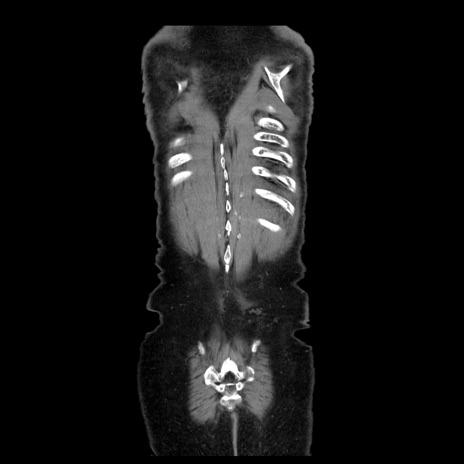

症例21(冠状断像)

【症例】70歳代男性

【主訴】腹痛

【現病歴】肝硬変・肝細胞癌にてかかりつけの方。約9時間前に食後より腹痛出現。症状が徐々に増悪し、嘔吐出現したため来院。

【既往歴】肝硬変、肝細胞癌(RFA、TACE後)

【身体所見】意識清明、表情苦悶様、BT 36℃、BP 129/78mmHg、P 88bpm、SpO2 97%(RA)、右上腹部から心窩部にかけて圧痛あり、反跳痛なし、筋性防御あり。

【データ】WBC 5800、CRP 0.16